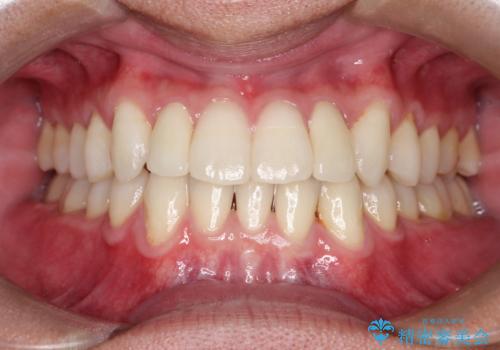

矮小歯といわれる通常よりも小さい歯であったので、こちらにオールセラミッククラウンを装着して自然な歯の形にすることにしました。

- 約22万円(スタンダード×2本)費用は治療当時の料金となります

上の前から2番目の歯を少量削らなければならないデメリットはありますが、クラウンの装着により自然な形へすることができました。